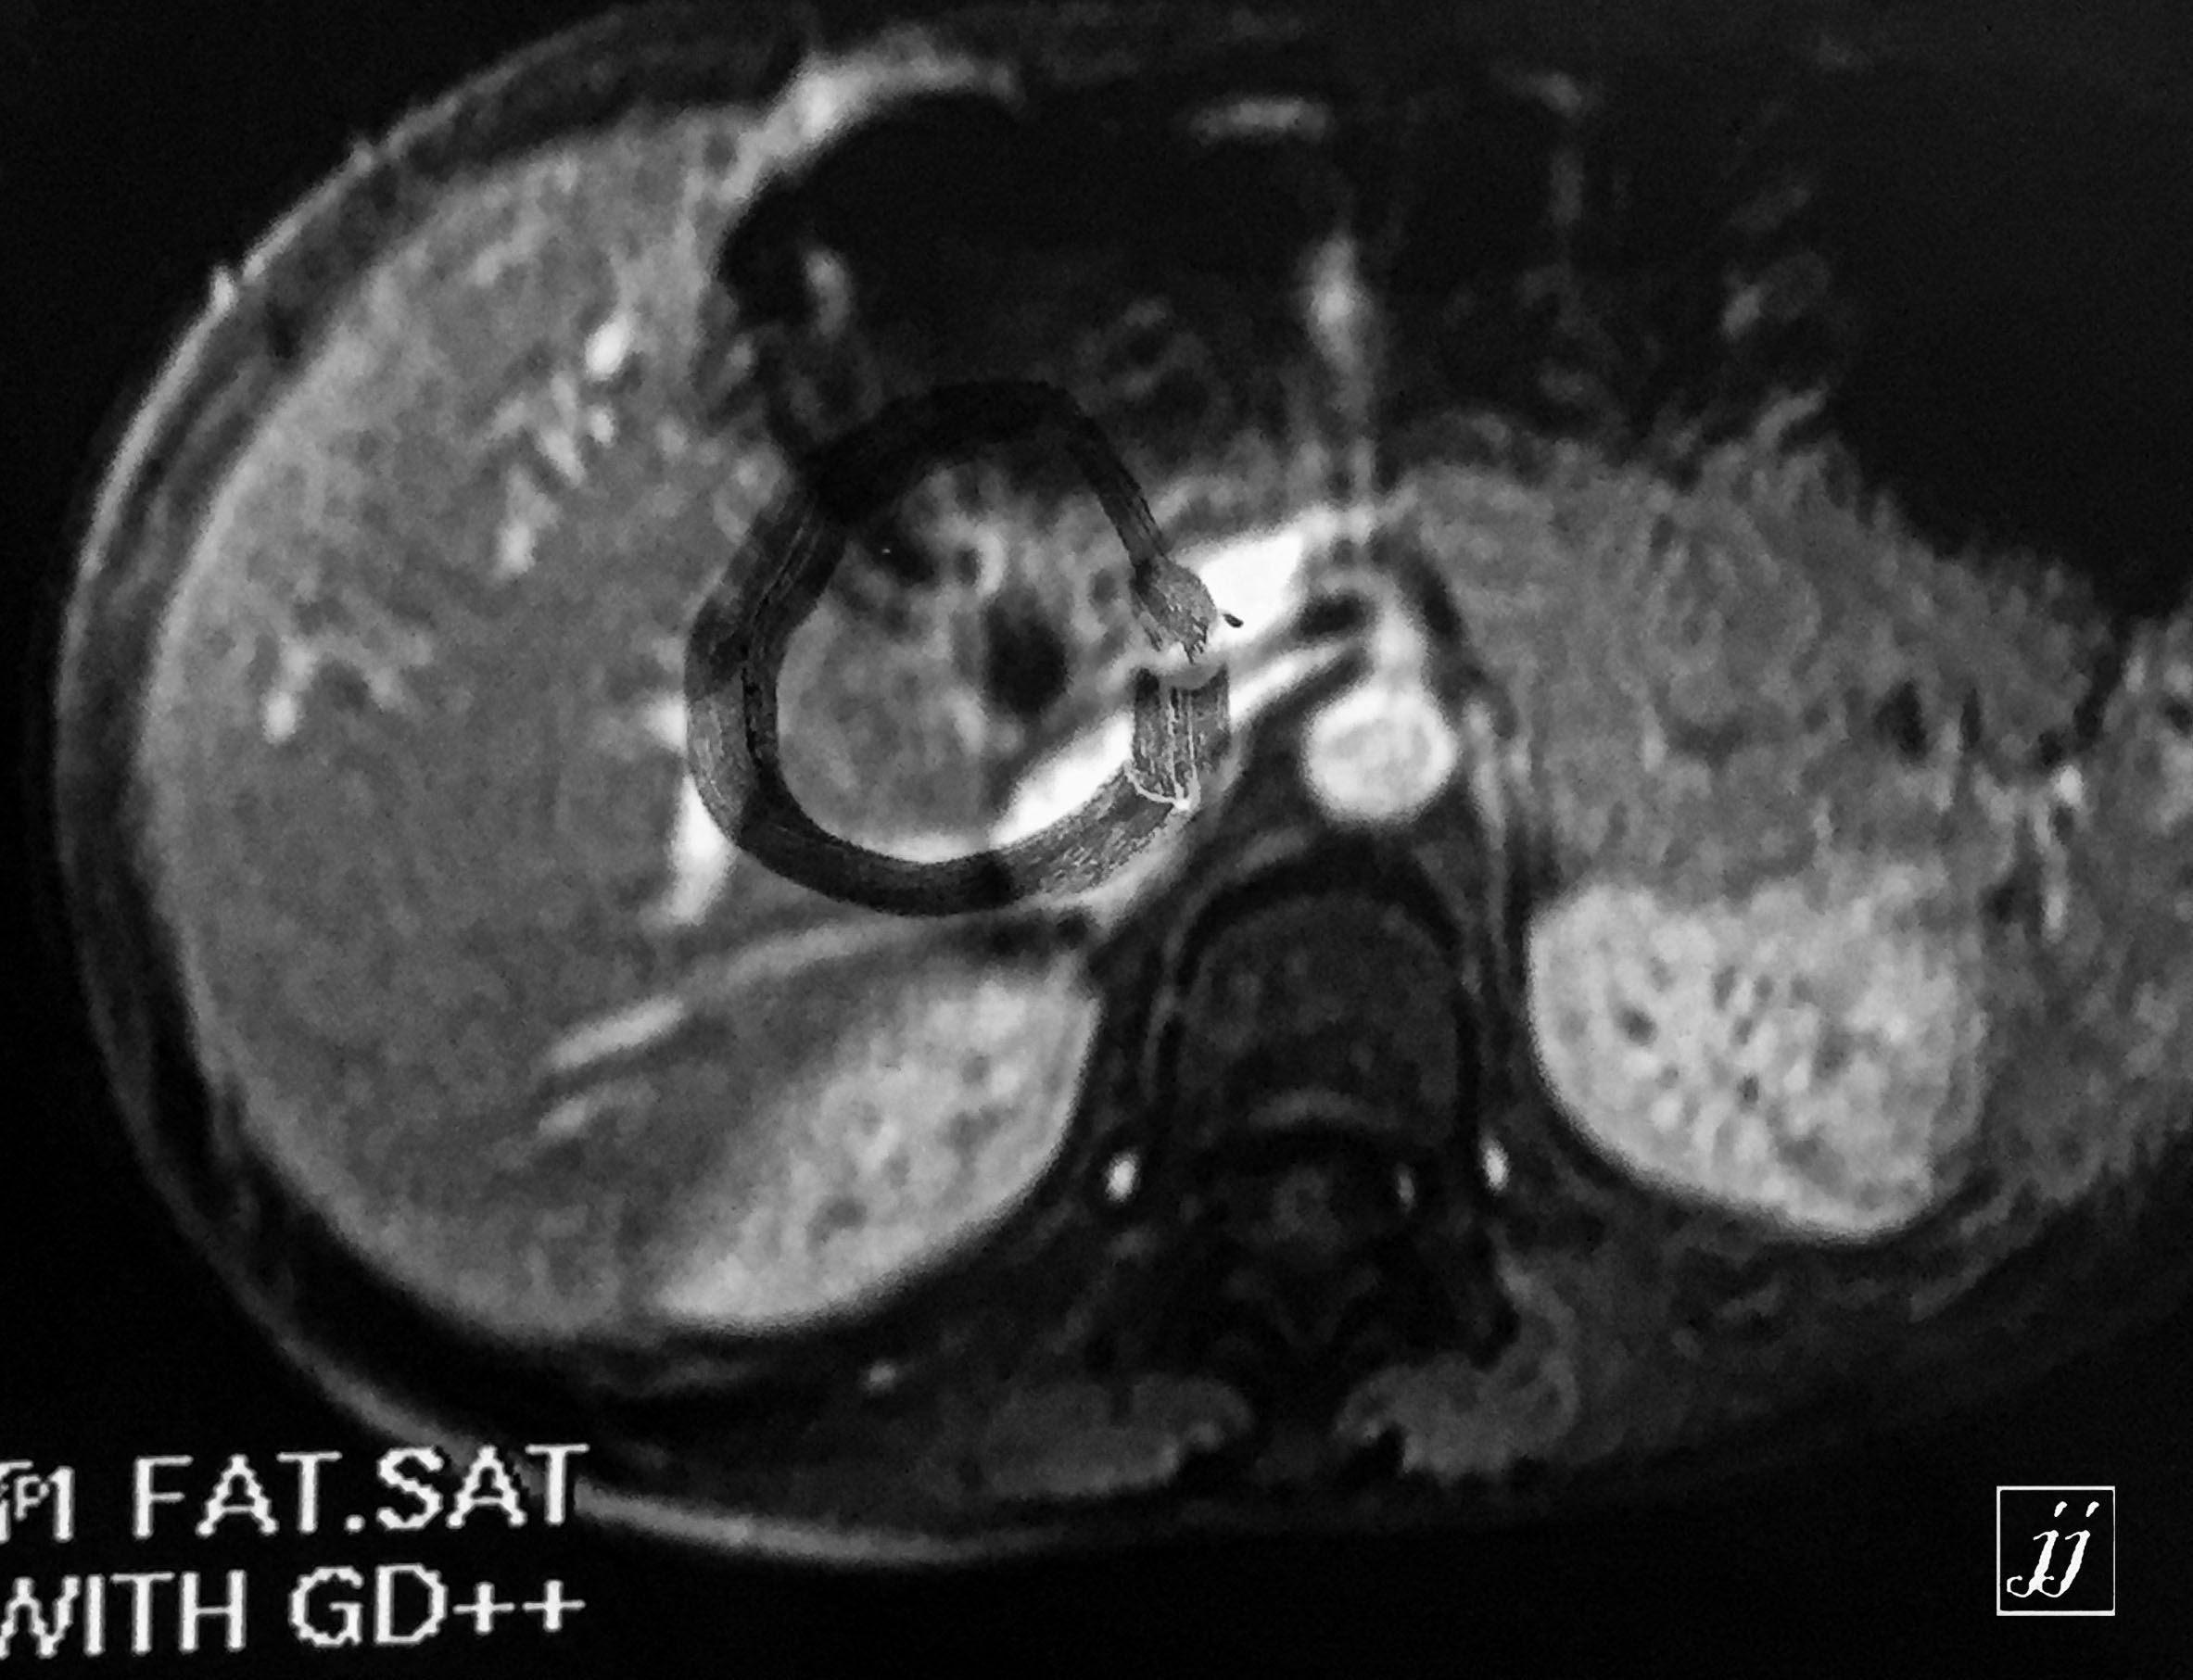

Abdomen- multiple liver cyst (7)